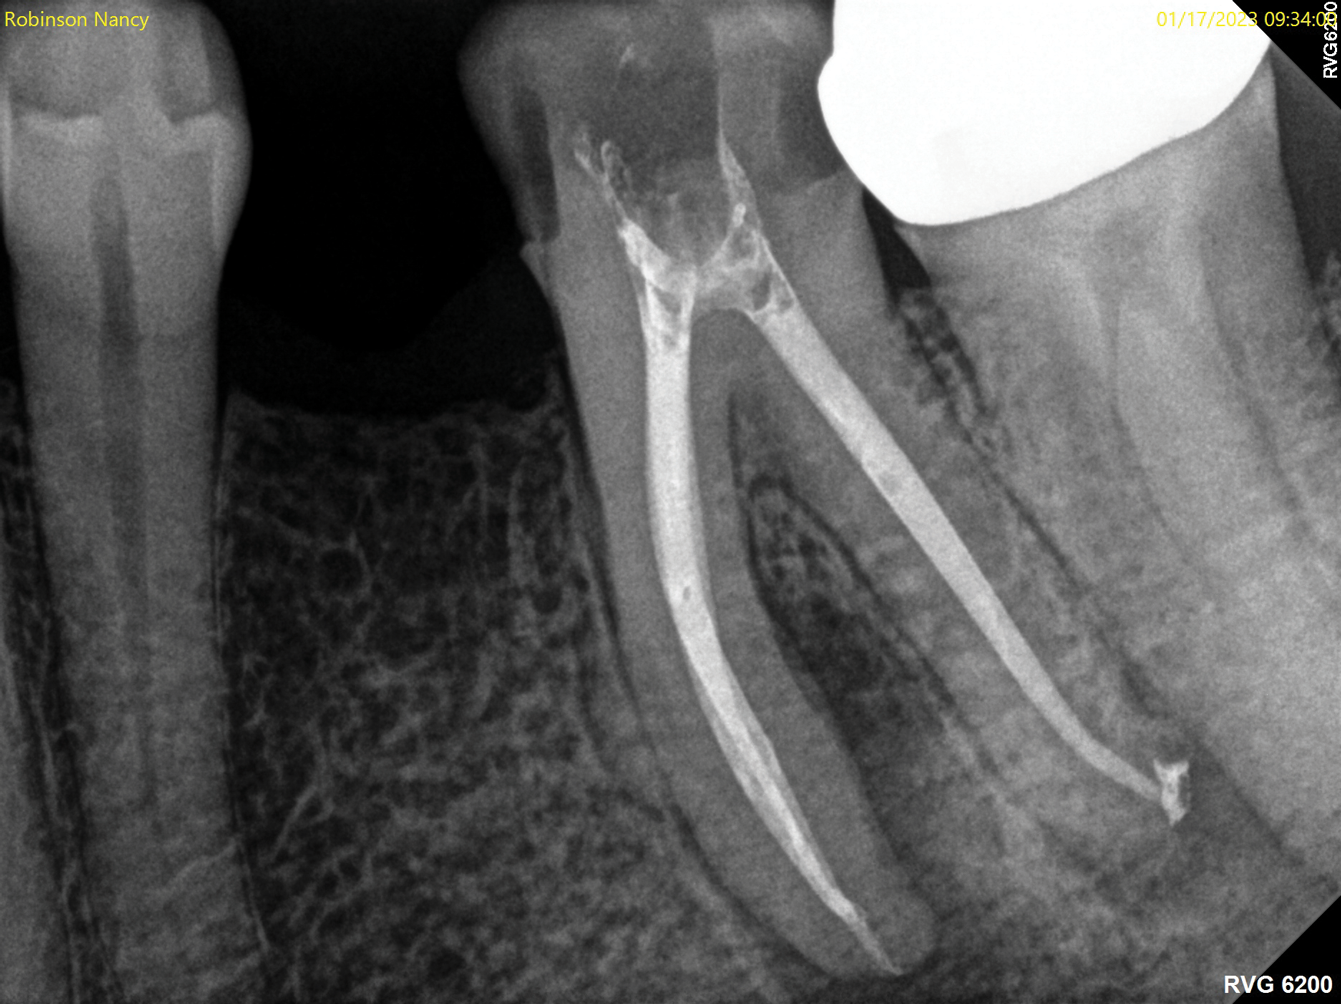

Fig 2. NSRCT can have high success, even with risk factors like periapical pathology associated, as depicted in this case presentation. Fig 1: Preoperative periapical radiograph showing AP. Fig 2: Preoperative CBCT. Fig 3: Immediate postoperative periapical radiograph. Fig 4: Three-month follow-up CBCT showing reduction of periapical radiolucency. Fig 5: One-year follow-up periapical radiograph showing resolution of periapical radiolucency.

Figure 2

Fig 1 through Fig 5. NSRCT can have high success, even with risk factors like periapical pathology associated, as depicted in this case presentation. Fig 1: Preoperative periapical radiograph showing AP. Fig 2: Preoperative CBCT. Fig 3: Immediate postoperative periapical radiograph. Fig 4: Three-month follow-up CBCT showing reduction of periapical radiolucency. Fig 5: One-year follow-up periapical radiograph showing resolution of periapical radiolucency.

The quality of the initial NSRCT is inversely associated with RETX outcomes, with poorer quality initial treatment tied to more predictable retreatment (Figure 6 through Figure 8).23 Inadequate quality of the initial NSRCT (eg, untreated anatomy, under-instrumentation, ledged and underfilled canals, and overextended obturation) was associated with greater predictability following RETX. However, if clinicians cannot identify and correct the mistakes made in the previous root canal therapy, it becomes more challenging to improve treatment outcomes.23